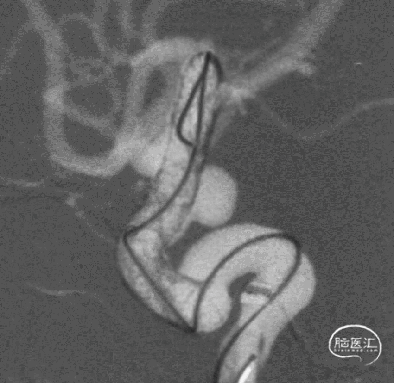

治疗结果

5、FD植入后,动脉瘤明显造影剂瘀滞,效果显著。

6、Tubridge Plus材料改进后通体显影,可以更好观察支架的贴壁性及术中打开情况,提高释放安全性。